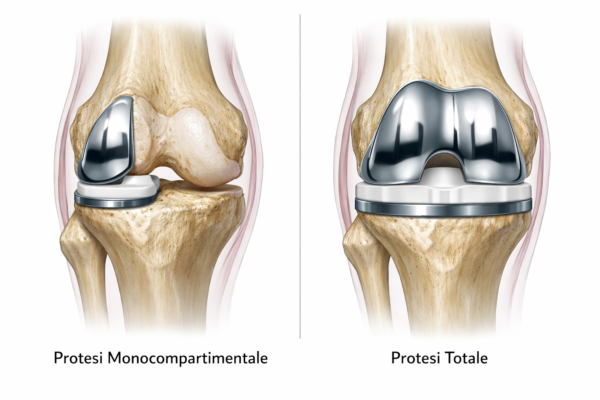

Introduzione: La protesi monocompartimentale di ginocchio (Unicompartmental Knee Arthroplasty, UKA) è una procedura efficace nel trattamento dell’artrosi limitata a un compartimento, con vantaggi potenziali rispetto alla TKA in termini di recupero funzionale, preservazione ossea e cinematica più fisiologica. Il successo è fortemente dipendente dalla corretta selezione del paziente e dall’esecuzione tecnica.

La UKA nasce come soluzione per pazienti con artrosi confinata a un compartimento (più frequentemente il mediale), con l’obiettivo di sostituire solo la parte malata preservando osso, legamenti e parte della cinematica nativa. Rispetto alla TKA, è associata (in pazienti ben selezionati) a minore invasività, recupero più rapido, migliore propriocezione e maggiore “sensazione di ginocchio naturale”. Tuttavia presenta un profilo di fallimento più sensibile a errori di indicazione e tecnica, e richiede criteri di selezione rigorosi.

UKA vs TKA

A parità di corretta indicazione, l’UKA resta una procedura con risultati eccellenti nei “best responders”, ma con un profilo di fallimento più sensibile a variabili tecniche e di sistema (esperienza/volume). Per questo è utile distinguere i determinanti dell’outcome in fattori legati al paziente, all’impianto, all’esecuzione chirurgica e all’organizzazione.

Risultati attesi e confronto con TKA: funzione vs revisione

Nei pazienti ben selezionati, l’UKA può offrire recupero più rapido e una cinematica percepita come più fisiologica. Tuttavia, su larga scala, i registri e diverse analisi comparative mostrano tassi di revisione mediamente superiori rispetto alla TKA, con ampia variabilità tra centri e operatori. In una meta-analisi che confronta revisioni in studi clinici e registri, l’UKA risulta associata a revisioni complessivamente più alte rispetto alla TKA (ordine di grandezza ~2x, dipendente da setting e definizioni).

Implicazione pratica: l’UKA non va “venduta” come TKA più piccola, ma come procedura diversa, molto premiante se indicata ed eseguita correttamente.